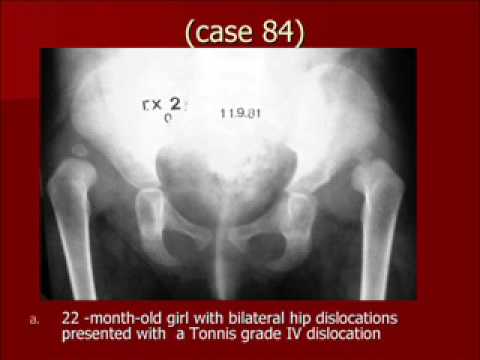

Developmental Dysplasia of the Hip the modified Hoffmann Daimler Method

This talk is a review of Developmental Dysplasia of the Hip. It discuss different treatment methods including the modified Hoffmann Daimler Method.